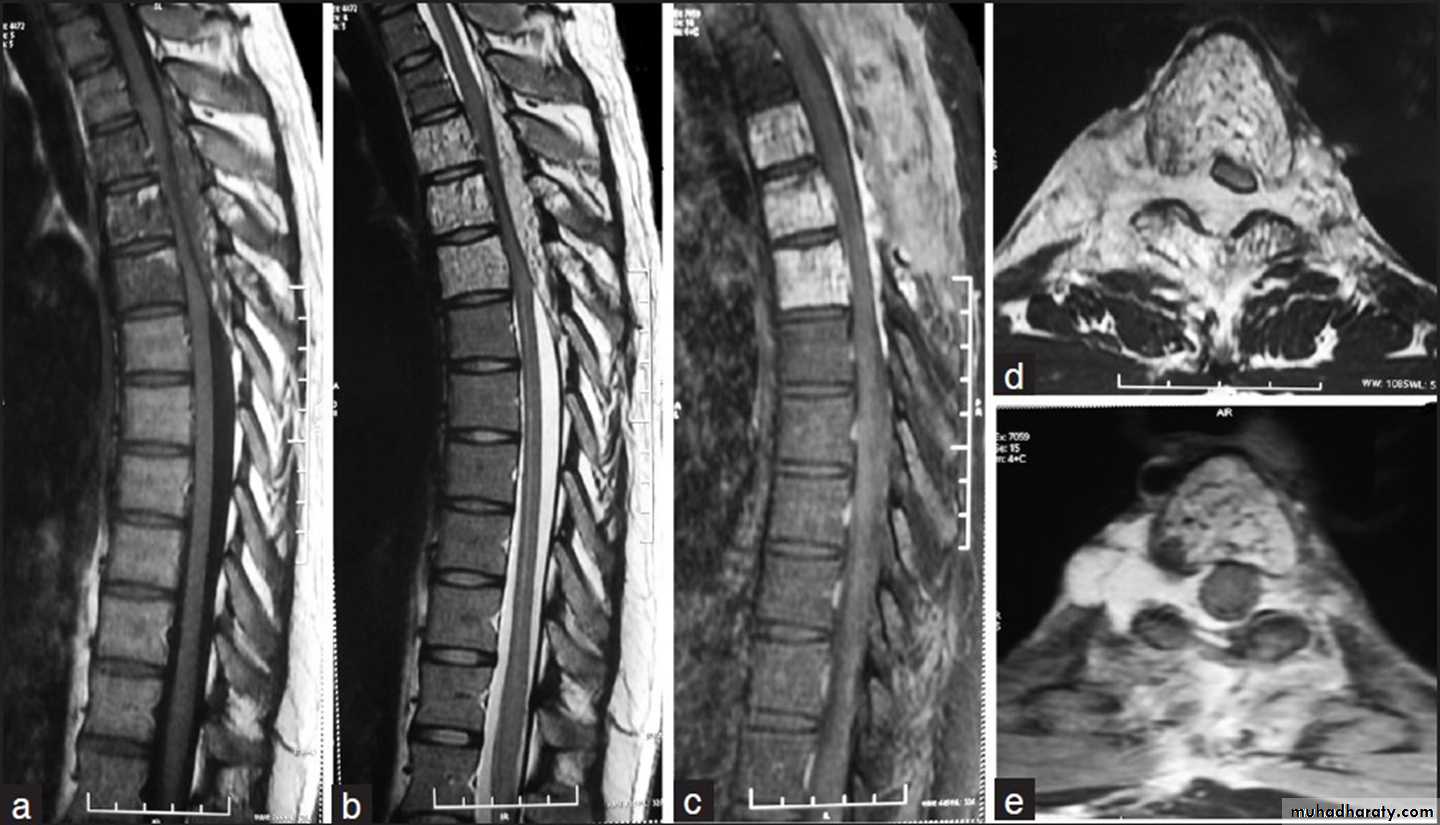

Sagittal MR image of the thoracic spine

demonstrates destruction of the intervertebral disc at the point where the paraspinal widening is maximal and this change is associated with alteration ofsignal from the vertebrae.

Haemangioma of the vertebral body of L3.

The whole body is marked by the characteristic vertical striationThe body of thoracic v. appeared as an area of high signal intensity on T1-T2-weighted images (a and b)